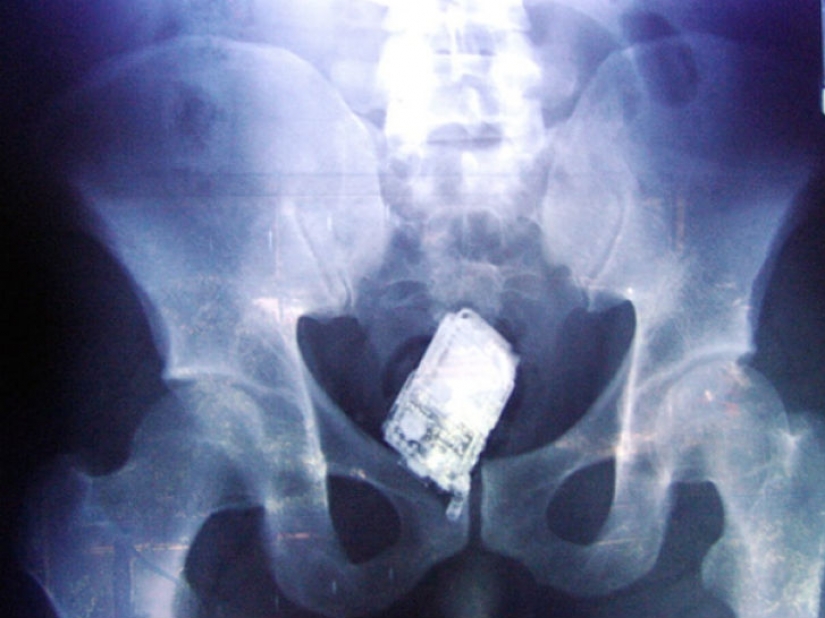

And the prisoners swallowed a cell phone.